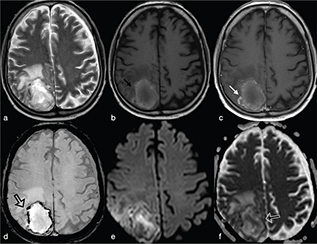

The abscess capsule is well-defined, smooth and complete. It shows a layered aspect, hypointense on FLAIR/T2-wi and hyperintense on T1-wi. The presence of collagen fibres and macrophages releasing free radicals are considered responsible for the short T1 and T2 of the rim due to their paramagnetic effect (Figure 2).7 The external low-signal rims on T2-wi could be useful to distinguish abscess from glioblastomas: in this case the rims, irregular or incomplete in the majority of cases, result from the store of haemorrhagic products surrounding the outer layer of the necrotic core.8

FIG 2. Nocardia Abscess in a 64-Year-Old Immunocompromised Man Presenting with Headache. A round lesion with thick capsule hyperintense on T1w (a) and hypointense on T2w/FLAIR-T2w (b–c) is shown. The lesion is characterised by a core of restricted diffusion (d–e). Typical ring-enhancement is present after intra-venous Gd administration; the coronal scan also reveals the presence of multiple lesions (f). A discreet amount of perilesional vasogenic oedema is present too (a–e).

On FLAIR/T2-wi, the abscess is usually surrounded by vasogenic oedema. Moreover, FLAIR images can be useful to help improve the diagnosis of a subarachnoid rupture of the BA with subsequent meningitis (Figure 3). Satellite abscesses that give a polylobate appearance to the BA can occur (Figure 4).